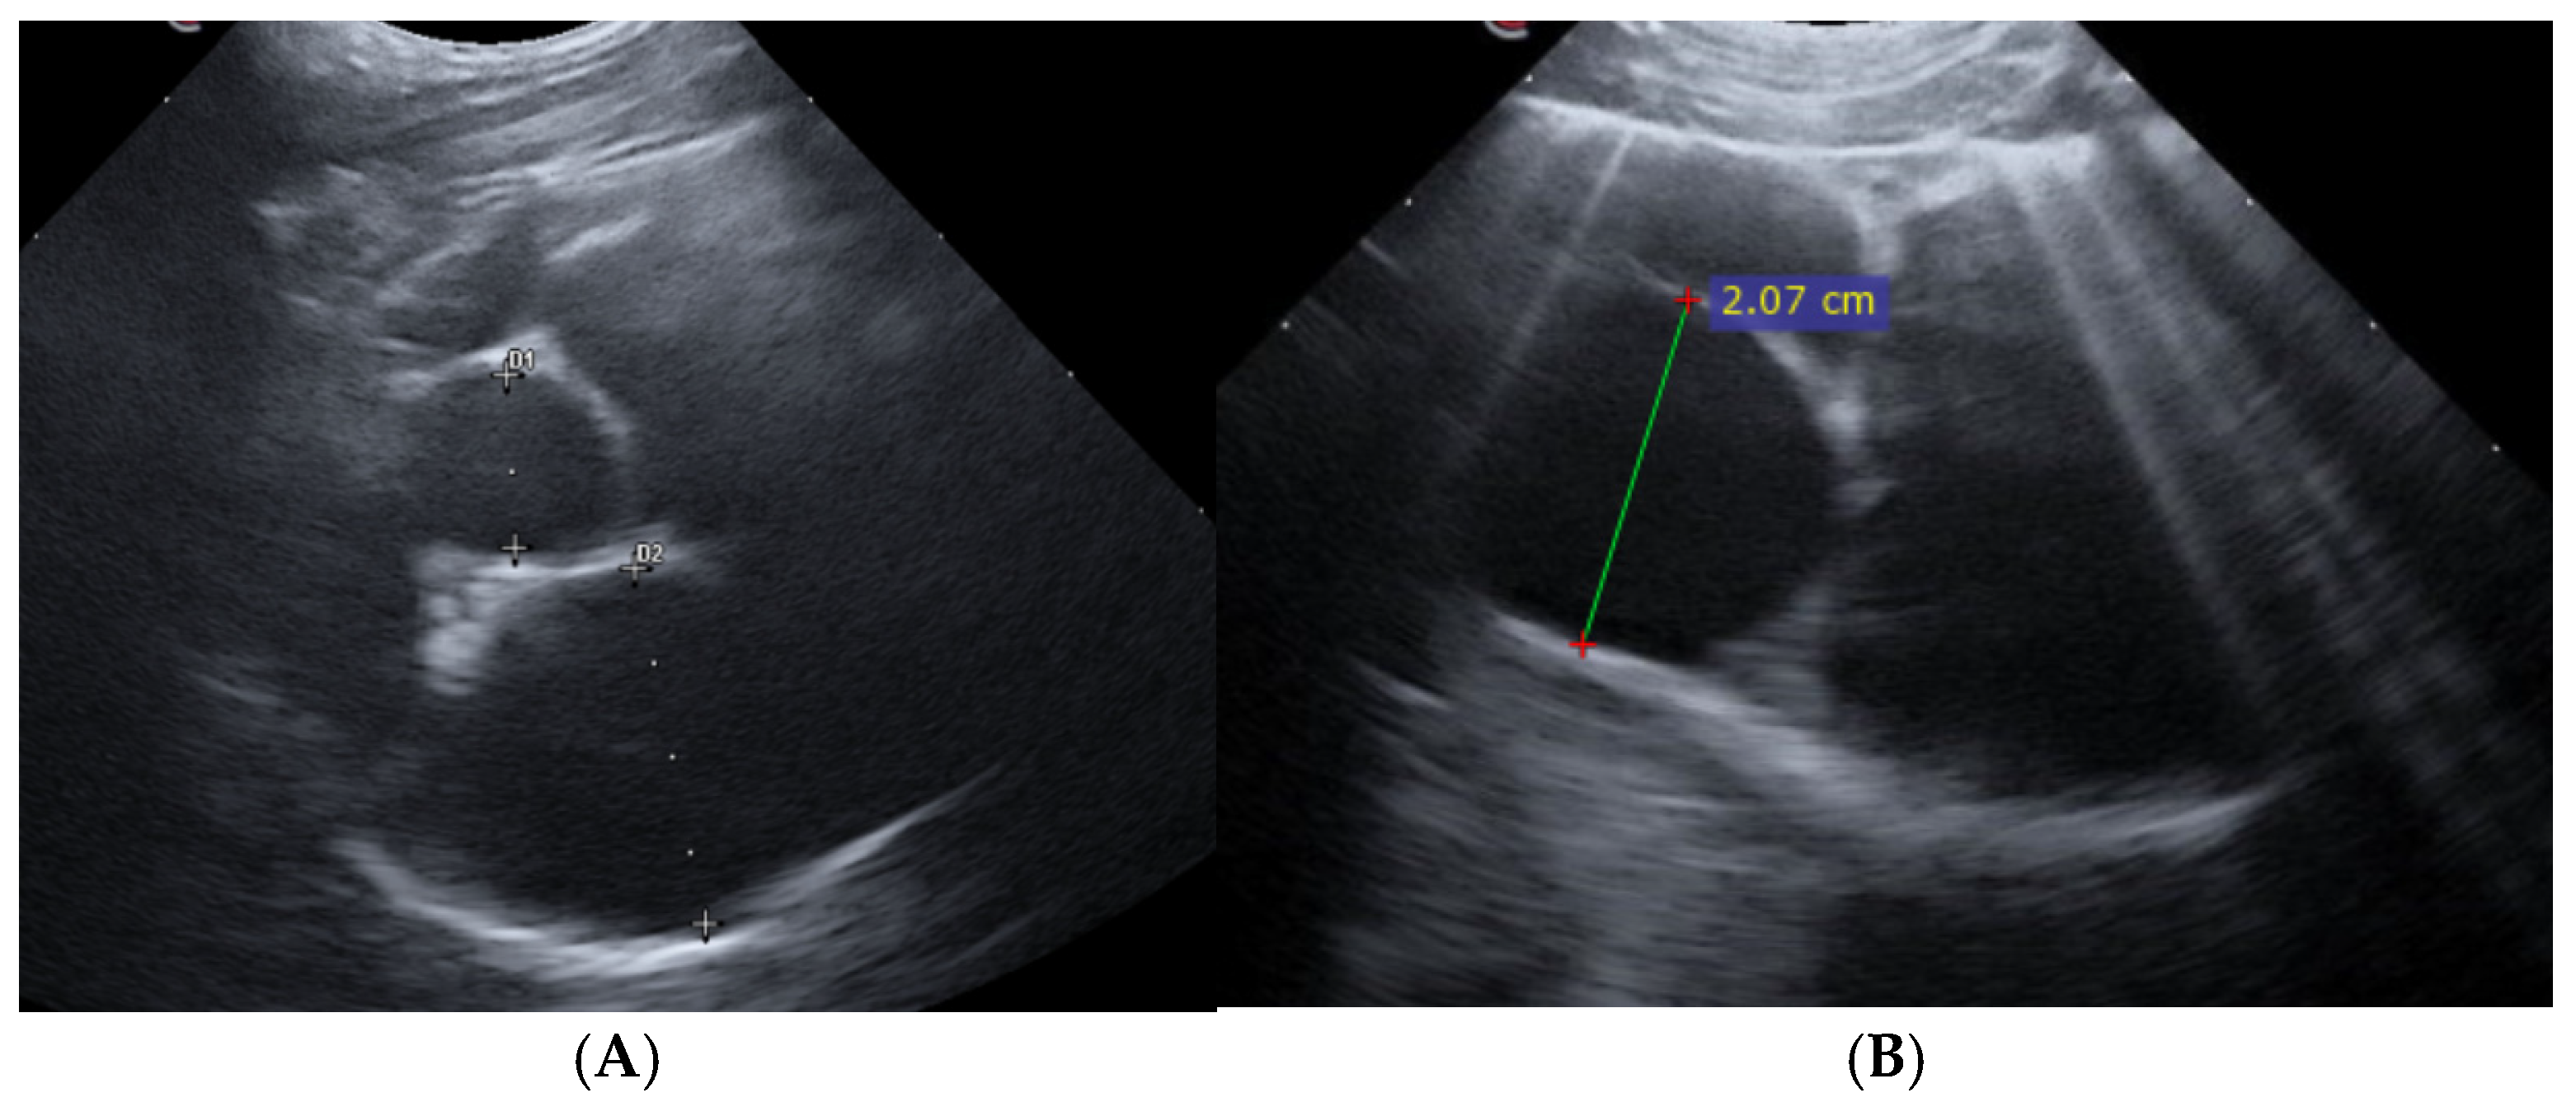

2.2. Point-of-Care Ultrasound Examination and Study Design